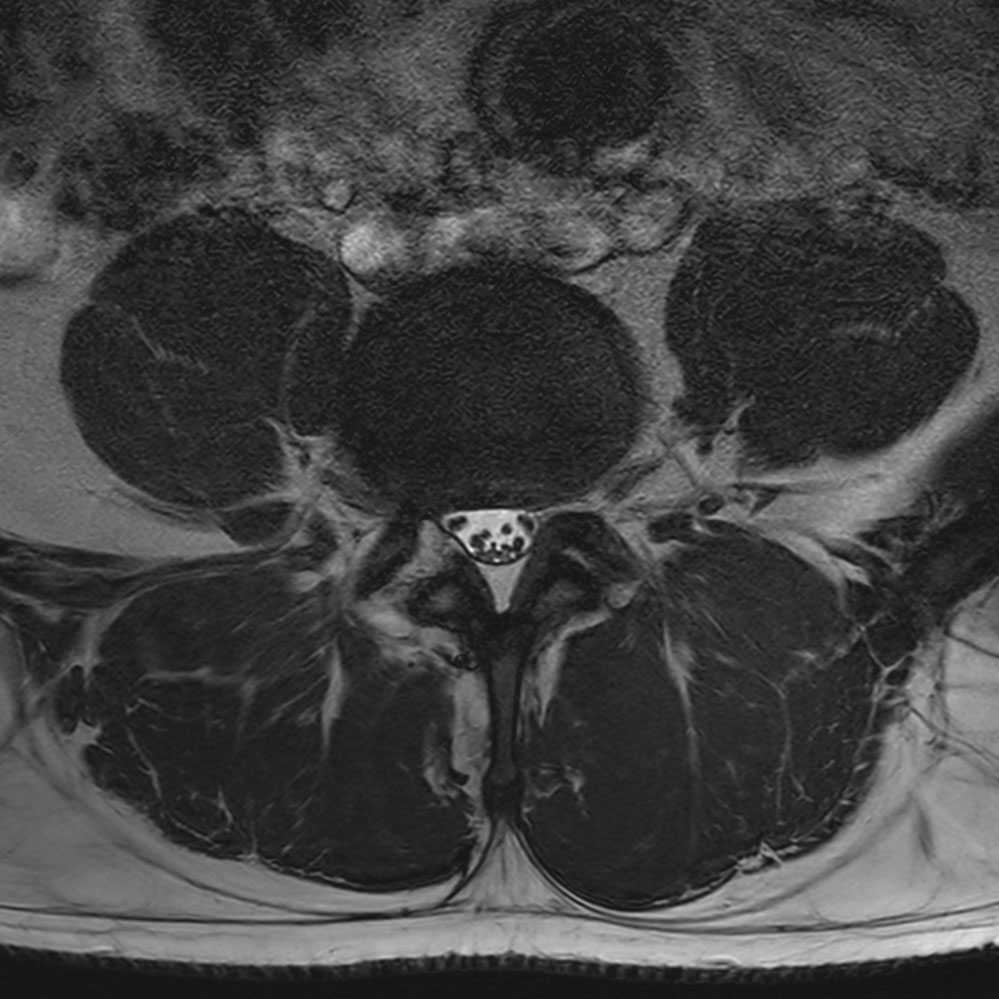

Patient with a lumbar spine bulging disc.

Axial bFFE